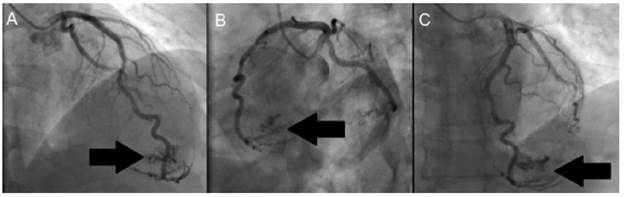

Then, invasive stratification was performed by left ventriculogram and selective coronary angiography (Figure 2 and 3), in which a dominant right coronary system with epicardial coronary arteries, without obstructive lesions and presence of a fistula of the distal anterior descending artery to the left ventricle was found.

Figure 2 shows extravasation of contrast medium into the apical territory irrigated by the anterior descending artery, while, in Figure 3, diagnostic injection on the left coronary artery shows posteroanterior projections (ARC 18°, RAO 25°) (Figure 3A), left oblique with caudal angulation (CAU 20°, LAO 49°) (Figure 3B) and left oblique with skull (CRA 18°, LAO 8°) (Figure 3C). Extravasation of contrast medium is also observed from the anterior descending artery to the left ventricle (black arrow).